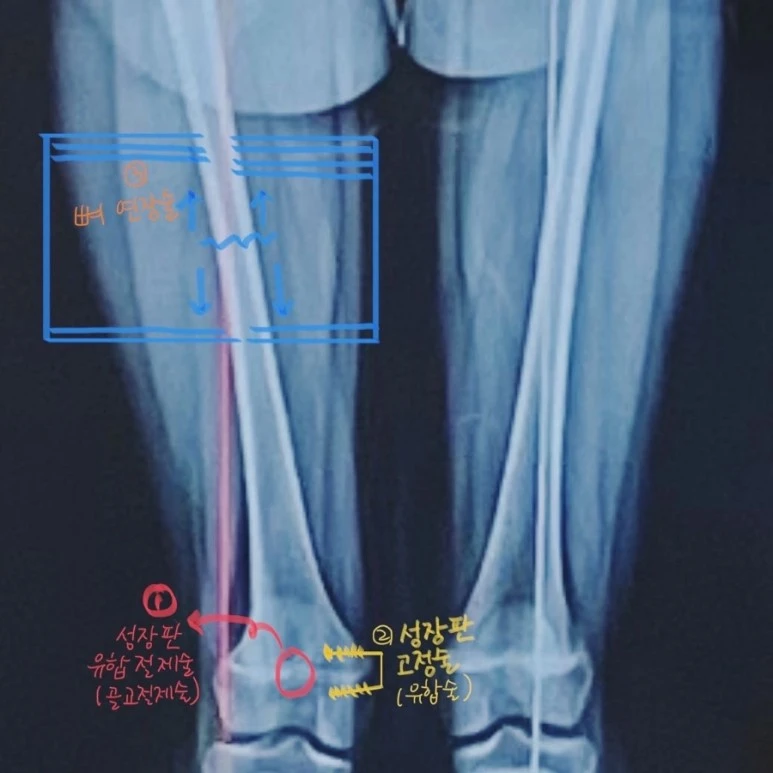

20230524%EF%BC%BF000443%EF%BC%BF379B58C9%EF%BC%8D158E%EF%BC%8D44B7%EF%BC%8D9E95%EF%BC%8D05B0BE1358E6.JPG?type=w773

내 간절함과 달리, 소아정형외과 전문의에게 들은 소견은 사진과 같다. 우리 아이는 육안으로도 뚜렷하게 이미 성장판 골절의 후유증으로 허벅지 뼈가 자라지 않고 있었고(당시 1cm 이상 양쪽 허벅지 길이 차이 남), 그 영향으로 외반 변형이라는 X자 다리가 다친 다리에서만 나타나고 있었다.

"성장판 유합절제술(골교절제술), 성장판 고정술을 진행해야 하지만, 저는 할 수 없습니다. 서울대 병원에 가보세요."